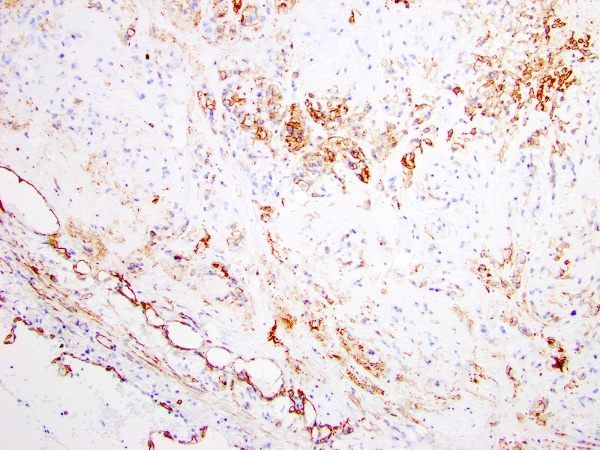

Immunohistochemical stains revealed that the tumor cells were positive for CD31, CD34, and ERG (Figure 3-5). The tumor cells did not mark with pancytokeratin, smooth muscle actin (Figure 6), epithelial membrane antigen, S-100 protein, HMB-45, SOX10, chromogranin, TTF-1 (Figure 7), PAX8, or desmin. No amyloid deposition was identified with Congo red stain.